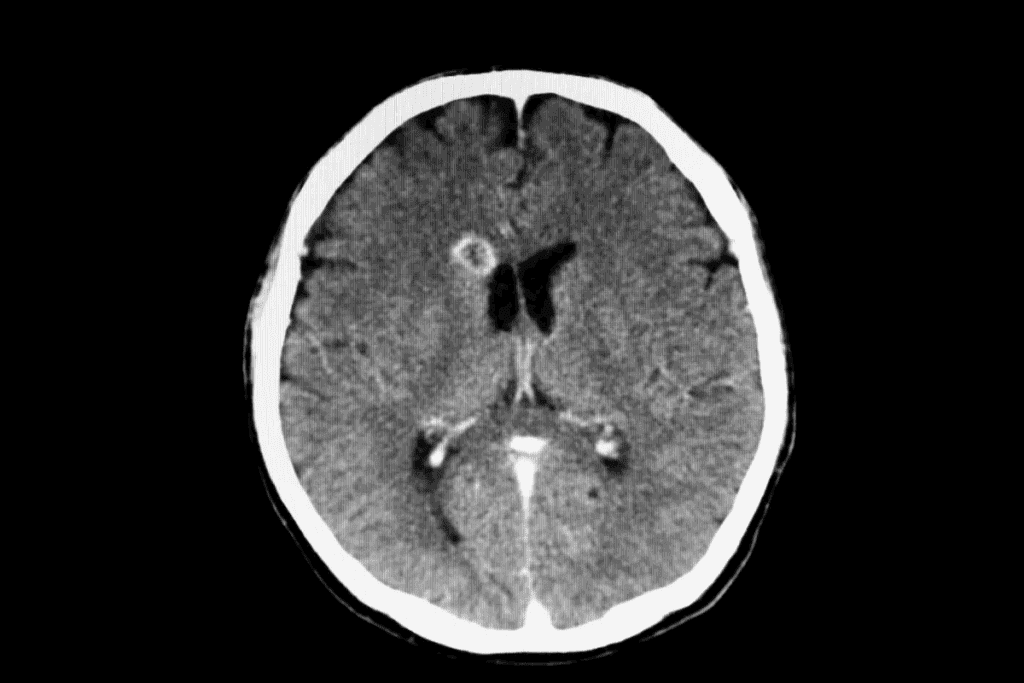

Tumors and Neoplasms

Tumors and neoplasms are abnormal growths in the brain. They can be either benign or malignant. These growths can cause problems because of their size, how they spread, or blockages in fluid pathways.

Imaging Techniques

Imaging techniques are vital for spotting brain lesions. The main ones are:

- Computed Tomography (CT) scans: CT scans give quick, detailed views of the brain. They help find lesions, bleeding, or other issues.

- Magnetic Resonance Imaging (MRI): MRI gives detailed images of the brain. It’s great for figuring out what kind of lesion it is, where it is, and how it affects the brain.

Biopsy Procedures

At times, a biopsy is needed for a clear diagnosis. This means taking a small piece of tissue from the lesion for study. The biopsy results help decide the best treatment.